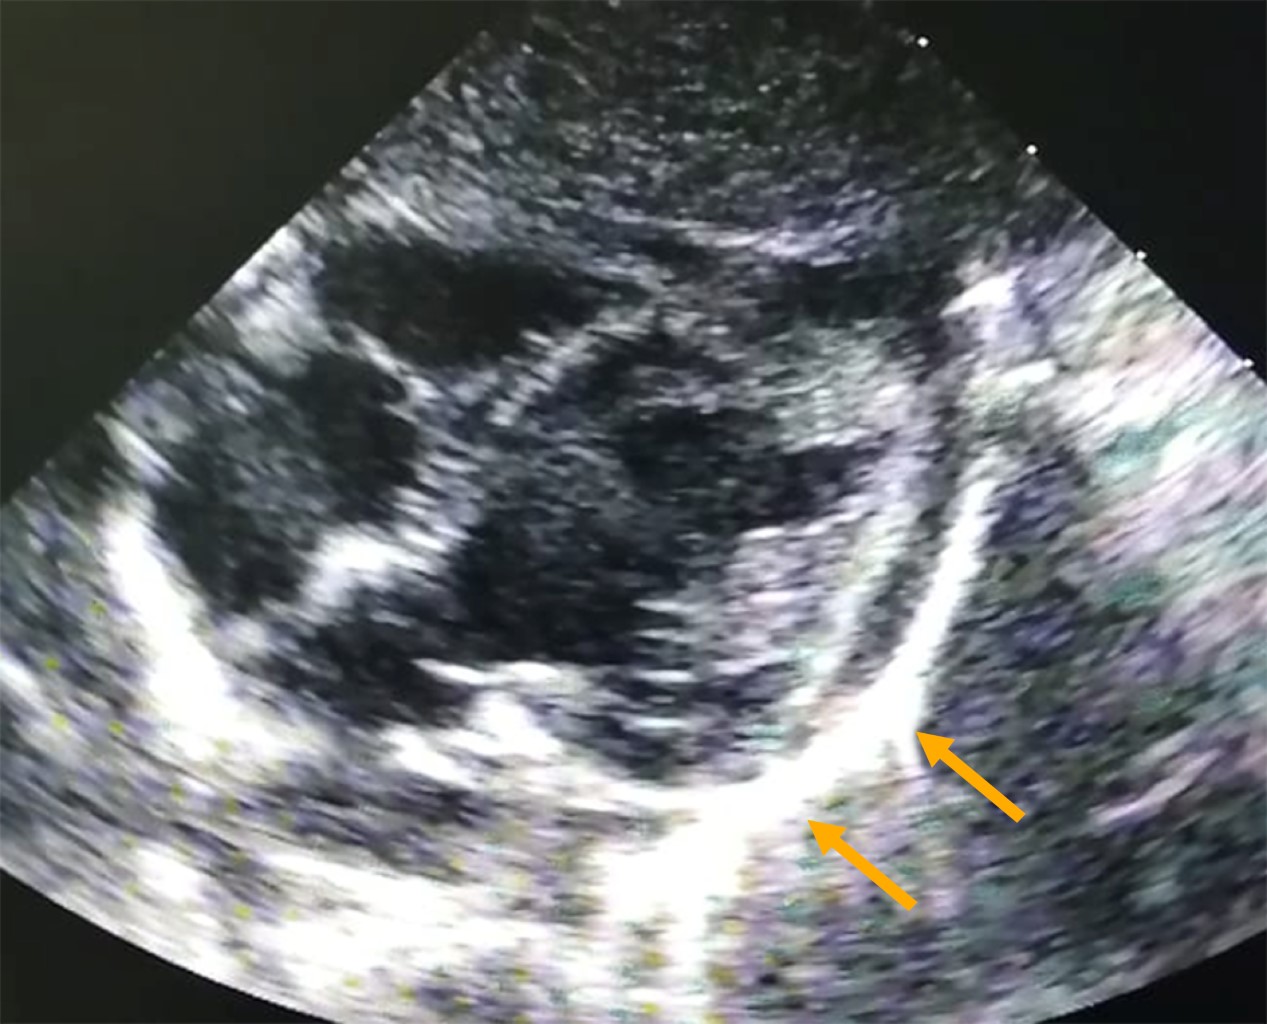

The echocardiogram showed normal artery coronary, LVEF 53% and refringent pericardial (Figure 1).

Figure 1